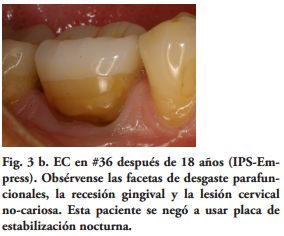

Al momento del examen, 10 (90.9%) EC estaban en función en 10 pacientes. Un molar 26, restaurado con EC, se perdió por enfermedad periodontal después de 12 años y 9 meses en función. Ninguna restauración se desprendió, no hubo recidiva de caries y al examen radiográfico no se observaron lesiones patológicas en los 10 DPET en función (Figs. 1a,1d; 2c; 3c,3d; 4c).

Por su parte, varios estudios clínicos, concluyeron que el remanente coronario es el factor más importante en el éxito clínico del DET (18-21). Por lo tanto, un criterio conservador es esencial en la preparación dentaria para un EC. Toda la superficie oclusal debe ser cubierta por la restauración, teniendo en cuenta la función oclusal del paciente. Los onlays transmiten fundamentalmente, fuerzas compresivas en la interfase adhesiva restauración - diente, mejorando el comportamiento biomecánico (22-24). Para este procedimiento restaurador fue sugerido un espesor oclusal de 3 mm. (25) y aumentando el mismo la resistencia a la fractura sería más alta (26). Además. si las paredes vestibular y/o palatina o lingual, tienen un espesor mayor de 2.0 mm., un chamfer de 1.2 mm. en oclusal de estas paredes, podrían tener un efecto zuncho o abrazadera, aumentando la resistencia a la fractura de los dientes y la retención de la restauración (Figs. 3a, 4a).

Las paredes internas de la corona dentaria y de la cámara pulpar, deben tener una divergencia hacia oclusal mayor de 60 y si presentan depresiones o zonas retentivas, deben rellenarse con cemento de ionómero de vidrio. El operador, dispensa una fina capa del mismo cemento en el piso cameral. En este estudio cuatro preparaciones tenían 3 paredes coronarias (Figs. 1b, 2a), cuatro 2 paredes (Fig. 3a) y en 2, las restauraciones abarcaban 4 paredes coronarias.

Mientras, en estudios clínicos y de laboratorio, los cementos resinosos de polimerización química y dual, tuvieron un mejor comportamiento que los fotopolimerizables y los de autograbado (38-44). Sin embargo, utilizando unidades de curado LED de alta potencia y aumentando el tiempo de exposición, a través de materiales cerámicos con diferentes espesores, recientes investigaciones de laboratorio han encontrado mayor grado de conversión y después de 24 horas, mayores valores de microdureza, en cementos resinosos fotopolimerizables y duales (45,46). Por lo tanto, los procedimientos clínicos y los cementos utilizados, pudieron haber influido en el Éxito Clínico obtenido (90%) (Figs. 1c, 2b, 3b, 4b).

En una publicación reciente (47), el bruxismo fue estadísticamente el factor de mayor riesgo de fracturas en DET. En esta investigación, 7 pacientes (70%) tenían o habían tenido historia de parafunción, lo que está en relativa concordancia con estudios epidemiológicos de bruxismo y DTM (48,49). Pero en el trabajo de Bindl y cols. (13), los pacientes con historia de DTM fueron excluidos de la muestra, lo que pudo haber mejorado los resultados clínicos del mismo.